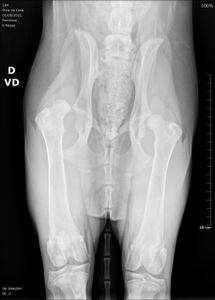

Minha cachorra tem 6 meses de vida se chama (Poca), filhote de Fila com Rottweiler, porte grande, pesa 19,500 Kg, foi adotada com um mês de vida e recentemente descobrimos que ela tem Displasia Coxofemoral, uma condição que acomete uma parcela de cães do porte dela, segundo o veterinário ela tem essa condição desde que nasceu que foi agravando com o tempo conforme ela cresce e fica mais pesada.

No caso dela o fêmur direito está completando deslocado do quadril e o esquerdo está com problema também, isso causa nela muita dor e dificuldade de locomoção, ela precisa de uma cirurgia que custa em média R$2.800,00, tem que fazer fisioterapia, provavelmente acupuntura, tem que tomar medicação para dor que também tem uma valor elevado. Infelizmente atualmente não tenho condição financeira para custear esse tratamento dela, por isso venho pedir ajuda de vocês por meio dessa vaquinha. Todo e qualquer valor arrecado será usado somente para tratamento dela.